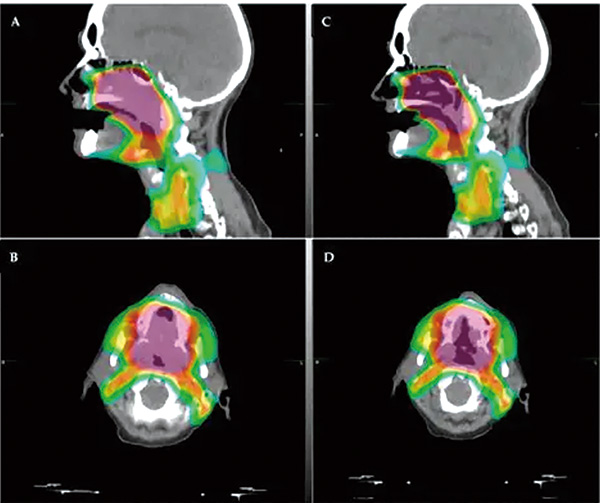

为了评估IMRT的头颈癌患者中放疗与嗅觉功能的相关性,包括嗅觉功能随时间的变化,该项非随机化临床试验招募了2021年1月1日至2023年12月1日组织学确诊并接受IMRT治疗的头颈癌患者。计划接受放疗的患者在多个时间节点接受TWSIT量表的嗅觉功能评估。鼻腔内镜用于排除混杂性的鼻腔疾病(如严重鼻中隔偏移、慢性鼻窦炎、头部外伤或头部放疗史)。主要终点为嗅觉评分与嗅觉区辐射剂量间的相关性。

总体来看,放疗后嗅觉功能评分下降,部分患者在随访期间有部分恢复。小剂量放疗的患者通常保持稳定的嗅觉功能。放疗剂量与嗅觉功能障碍中度正相关。放疗剂量每增加1 Gy,TWSIT评分下降0.128(0.083~0.173)。受试者工作特征分析确定,22 Gy为估算嗅觉障碍的潜在阈值,此时曲线下面积为0.74(95%CI 0.52~0.96,P=0.03),敏感性为64%,特异性为92%。

在11例出现嗅觉功能障碍的患者中,5例的放疗剂量≤22 Gy,6例的剂量较大。多变量分析显示,嗅觉区域平均放疗剂量超过22 Gy是唯一的独立风险因素(OR=20.65,95%CI 2.60~164.35)。部分接受大剂量放疗的患者出现长达1年的持续性的嗅觉功能障碍。根据敏感性和特异性,嗅球部位放疗剂量≤22 Gy或有超过90%的概率避免嗅觉功能障碍。